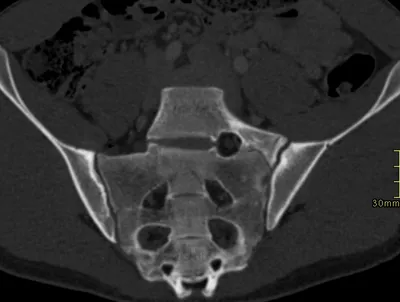

- This collection contains 5 radiology images related to dysplasia, including various imaging modalities such as X-rays, MRIs, CT scans, and ultrasound images commonly used in medical diagnosis and education.